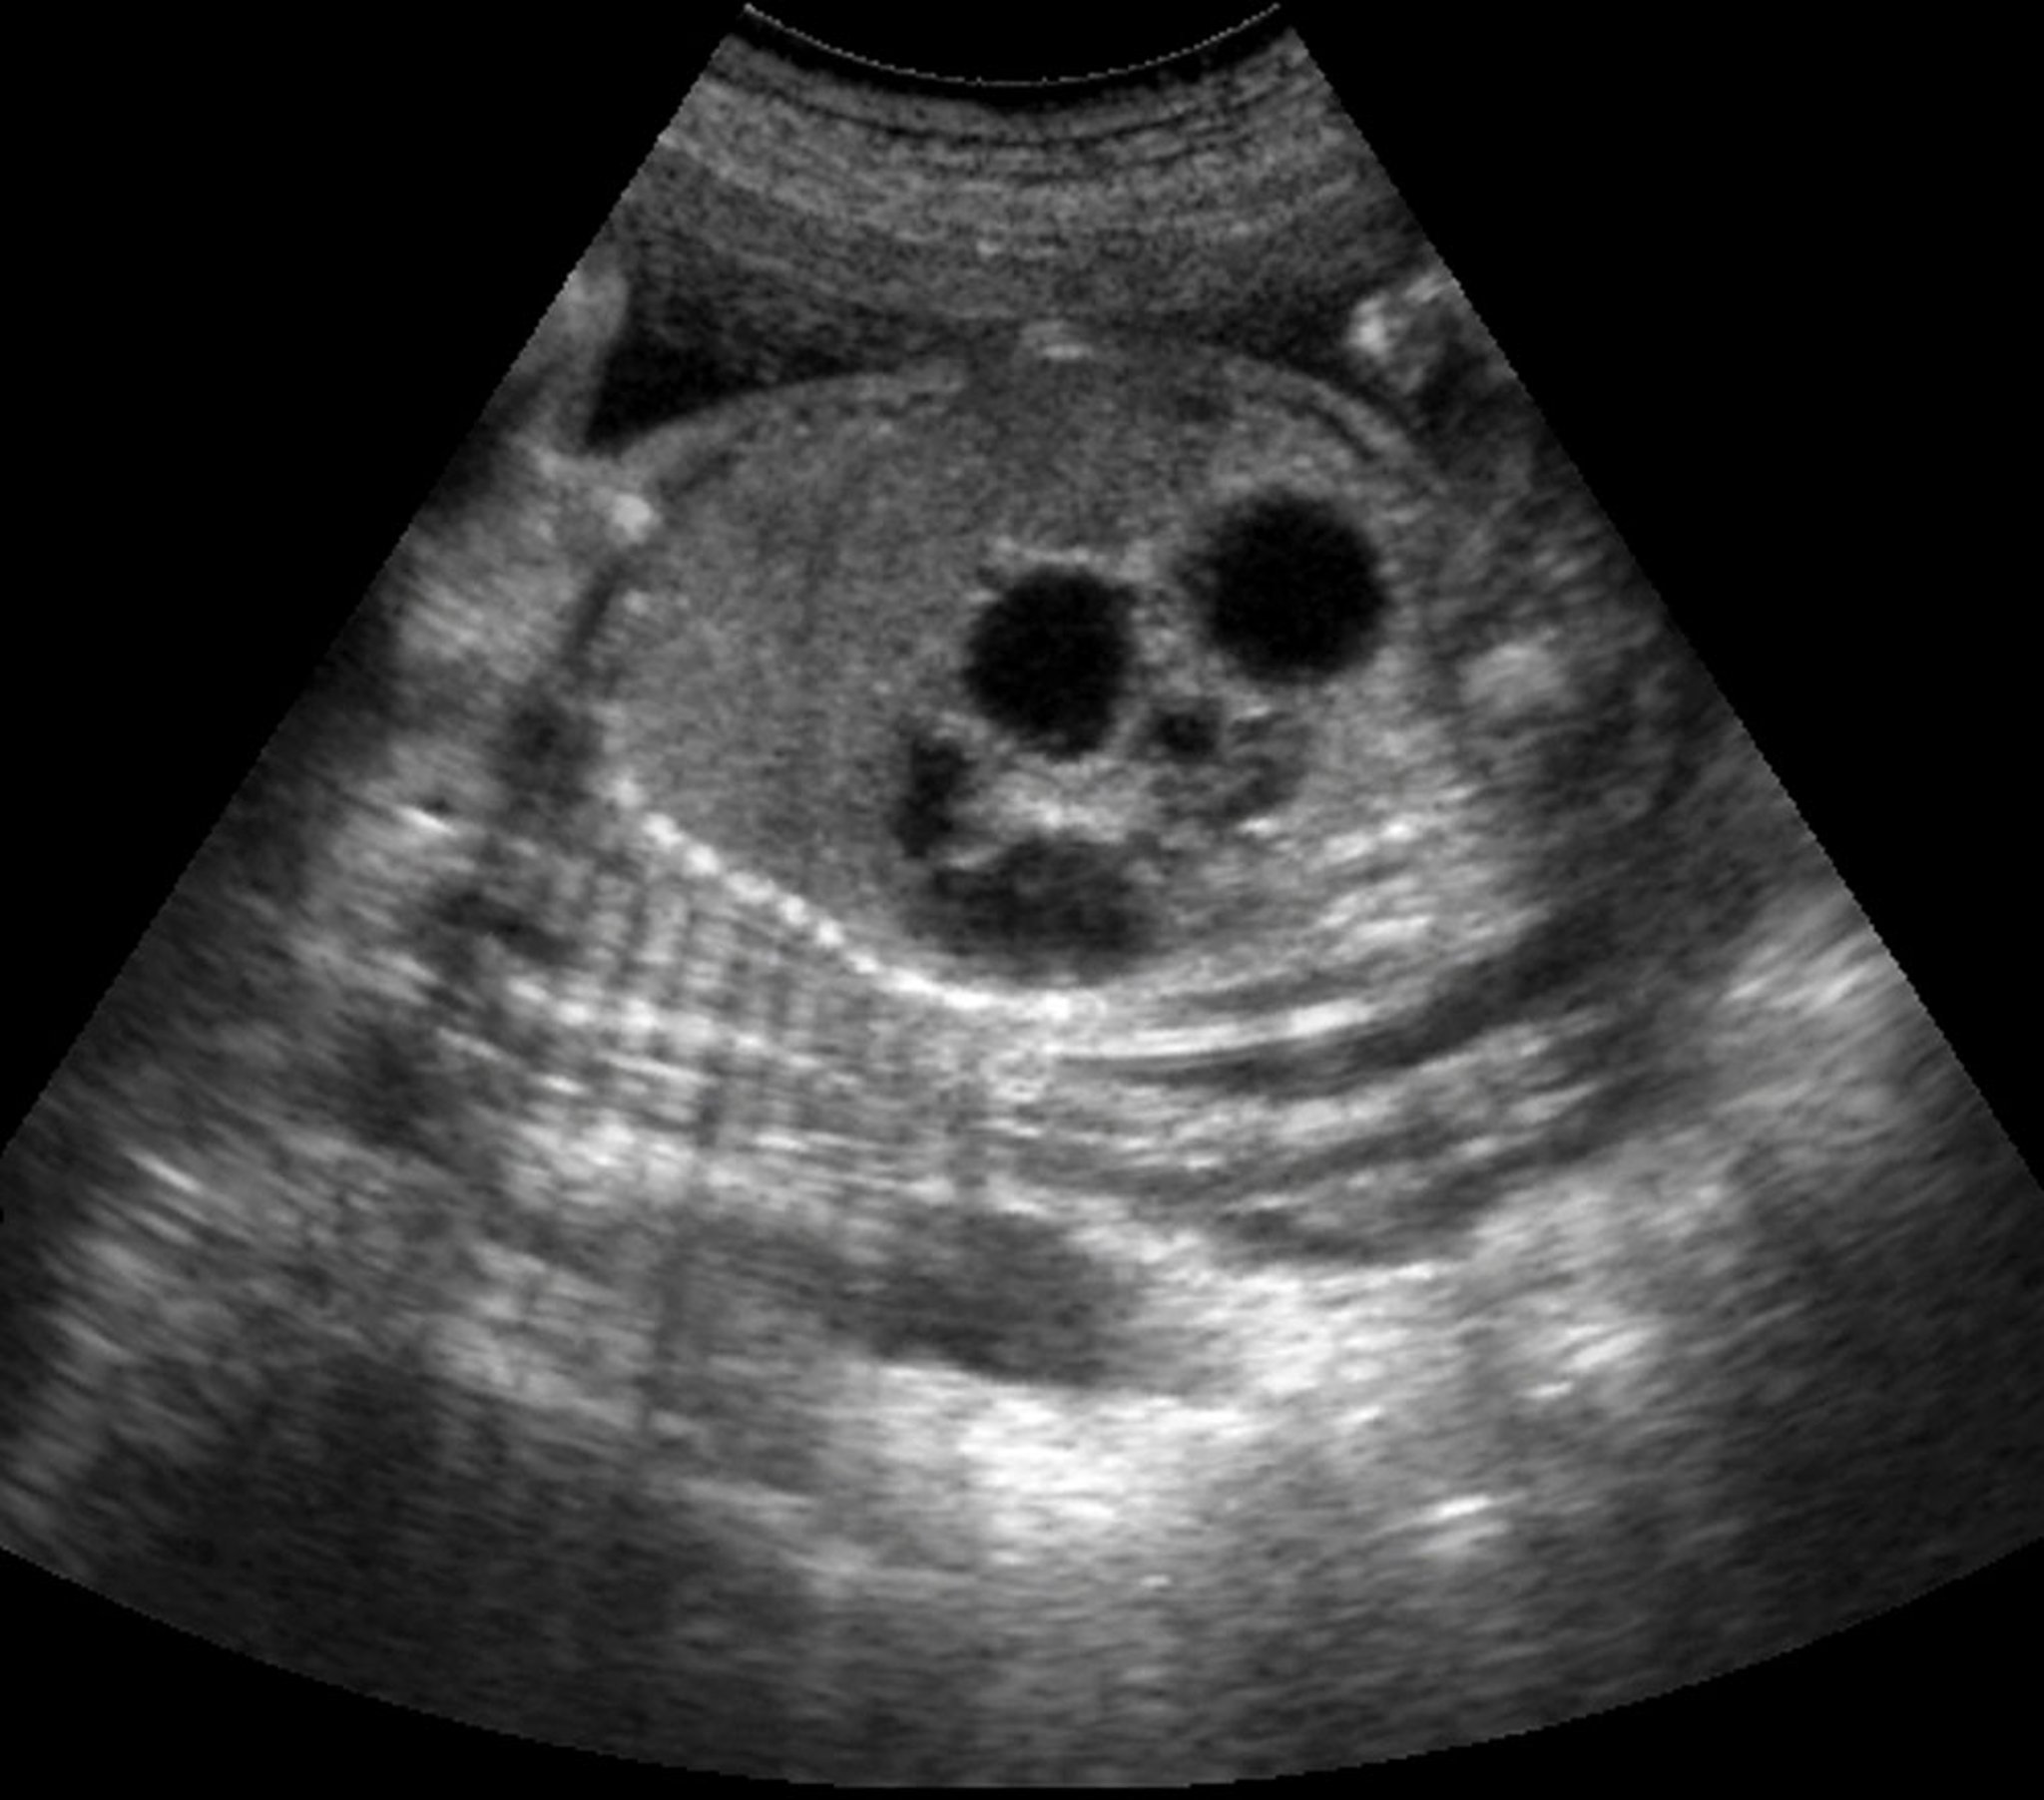

Diagnosis of duodenal atresia is suspected prenatally if there is polyhydramnios and/or a dilated stomach. Prenatal ultrasound can detect a double-bubble sign (a large gastric bubble and a smaller proximal duodenal bubble) in up to 80% of cases (2).

Ефект «Double-Bubble»

This radiograph shows the typical double-bubble effect seen with complete duodenal obstruction. The smaller bubble represents the proximal, dilated duodenum (white arrow); the larger bubble represents the stomach (black arrow).

This effect can be seen with duodenal atresia, duodenal web, annular pancreas, and preduodenal portal vein. Rarely, it can also be seen with complete duodenal obstruction resulting from Ladd bands in a patient with malrotation.